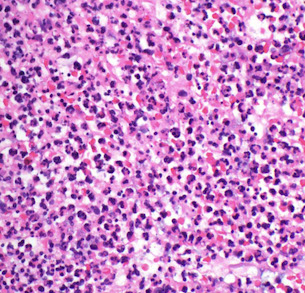

Histo: dense mononuclear infiltrate c foamy histiocytes and formation of Touton GCs

- overlying dermis looks flattened; inc eos common

IHC: (+) CD56 / HAM65, S100

JXG